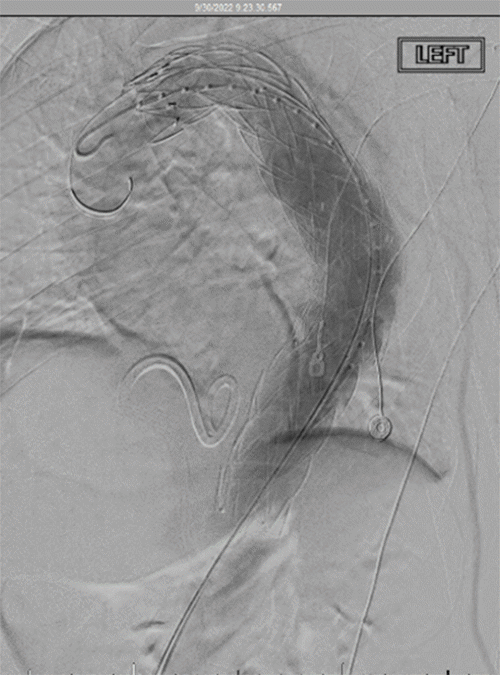

He was admitted to the trauma ICU for pain management and pulmonary hygiene assistance. A pigtail catheter was placed to drain a right hemothorax, and his fractures were managed conservatively without surgery. Due to the size of the TAA, a semi-urgent repair was considered. Risk stratification indicated a low cardiac risk for surgery. On hospital day 3, the patient underwent a thoracic endovascular aortic repair (TEVAR) with placement of a lumbar drain (Figure 2). The distal landing zone of the aortic stent-graft was positioned just proximal to the celiac arteries to ensure adequate aneurysm coverage.

Figure 2. Intraoperative Fluoroscopy Image. Published with Permission

Endovascular deployment of a stent-graft within the descending thoracic aortic aneurysm. The stent-graft extends to the level of the celiac artery. The left subclavian artery remains intentionally uncovered